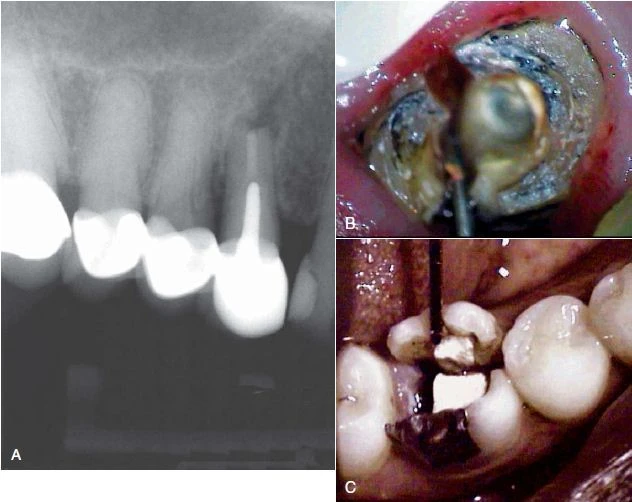

Hình 4. Thường khó chẩn đoán nứt dọc chân răng trừ khi là phải tháo bỏ miếng trám cũ

Phương pháp chiếu sáng và dùng thuốc nhuộm

Đôi khi cần phải tháo miếng trám trên răng để có thể quan sát vết nứt rõ hơn. Nhuộm bằng Xanh Methylene bằng cách bôi thuốc lên bề mặt răng bằng đầu tăm bông, thuốc nhuộm sẽ quyên qua vùng nứt và xác định vị trí đường nứt. Chiếu sáng cũng có thể hữu ích hơn bằng cách chiếu trực tiếp ánh sáng có cường độ cao vào bề mặt răng tại đường nối men – xi măng để xem mức độ lan rộng của vết nứt. Phần răng gần với nguồn sáng sẽ hấp thu ánh sáng và phát sáng, trong khi phần răng phía bên kia của vết nứt không được sánh sáng truyền qua sẽ có màu xám hơn. Mặc dù có thể phát hiện được vết nứt bằng thuốc nhuộm hoặc ánh sáng nhưng độ sâu của vết nứt không thể lúc nào cũng xác định được.

Hình 9. Đôi khi không có dấu hiệu rõ ràng cho thấy lý do răng có triệu chứng. (A) Hình ảnh X quang cho thấy răng cối lớn thứ hai hàm dưới có miếng trám sâu mức độ trung bình. (B) Thử tuỷ cho thấy răng chết tuỷ. Không chiếu sáng nên không thấy có đường nứt nào cả. (C) Chiếu ánh sáng có cường độ cao lên bề mặt răng, quan sát thấy vết nứt ở mặt ngoài. (D) Chiếu sáng vào mặt xa – trong của răng.